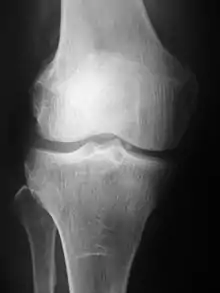

Projection (plain) radiography

Radiographs (originally called roentgenographs, named after the discoverer of X-rays, Wilhelm Conrad Röntgen) are produced by transmitting X-rays through a patient. The X-rays are projected through the body onto a detector; an image is formed based on which rays pass through (and are detected) versus those that are absorbed or scattered in the patient (and thus are not detected). Röntgen discovered X-rays on November 8, 1895 and received the first Nobel Prize in Physics for their discovery in 1901.

In film-screen radiography, an X-ray tube generates a beam of X-rays, which is aimed at the patient. The X-rays that pass through the patient are filtered through a device called a grid or X-ray filter, to reduce scatter, and strike an undeveloped film, which is held tightly to a screen of light-emitting phosphors in a light-tight cassette. The film is then developed chemically and an image appears on the film. Film-screen radiography is being replaced by phosphor plate radiography but more recently by digital radiography (DR) and the EOS imaging.[5] In the two latest systems, the X-rays strike sensors that converts the signals generated into digital information, which is transmitted and converted into an image displayed on a computer screen. In digital radiography the sensors shape a plate, but in the EOS system, which is a slot-scanning system, a linear sensor vertically scans the patient.

Plain radiography was the only imaging modality available during the first 50 years of radiology. Due to its availability, speed, and lower costs compared to other modalities, radiography is often the first-line test of choice in radiologic diagnosis. Also despite the large amount of data in CT scans, MR scans and other digital-based imaging, there are many disease entities in which the classic diagnosis is obtained by plain radiographs. Examples include various types of arthritis and pneumonia, bone tumors (especially benign bone tumors), fractures, congenital skeletal anomalies, and certain kidney stones.